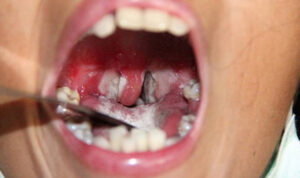

Biểu hiện bệnh có thể từ nhẹ đến nặng, thường có giả mạc màu trắng ở tuyến hạnh nhân, hầu họng, thanh quản, mũi, có thể xuất hiện ở da, kết mạc mắt, trường hợp nặng có thể gây biến chứng và tử vong. Tỷ lệ tử vong khoảng 5-10%. Bệnh bạch hầu có thể phát triển thành dịch nhất là ở trẻ dưới 15 tuổi chưa được gây miễn dịch đầy đủ. Cần lưu ý phân biệt với bệnh viêm họng có giả mạc mủ khác hoặc viêm amidan có hốc mủ.